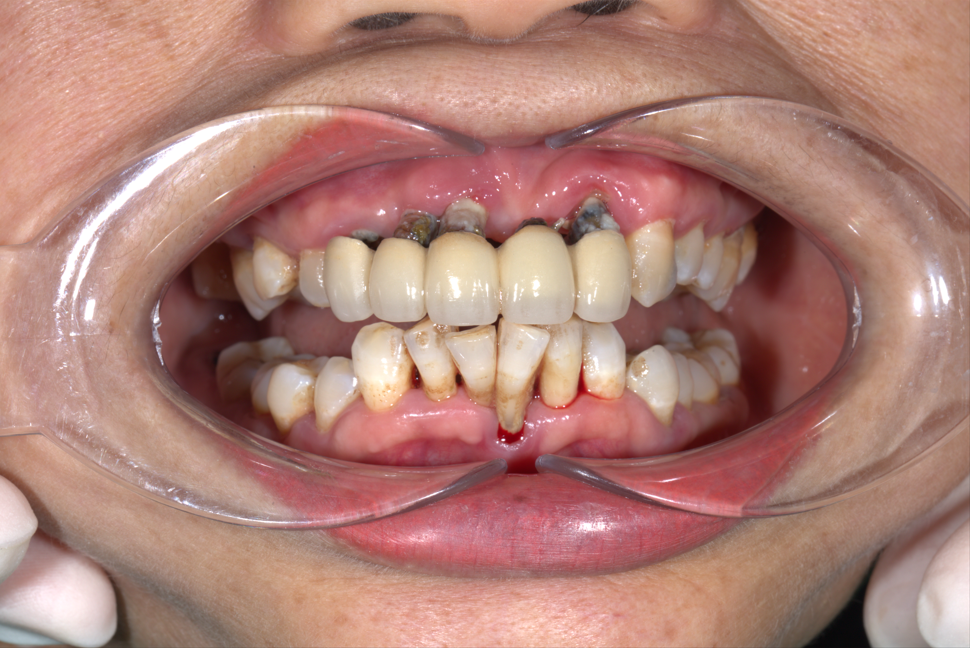

Làm cầu răng dài không thể ăn nhai được chú khách hàng quyết tâm chuyển sang Implant để ăn nhai tốt hơn

Cầu 7 răng → phương án A: 4 trụ